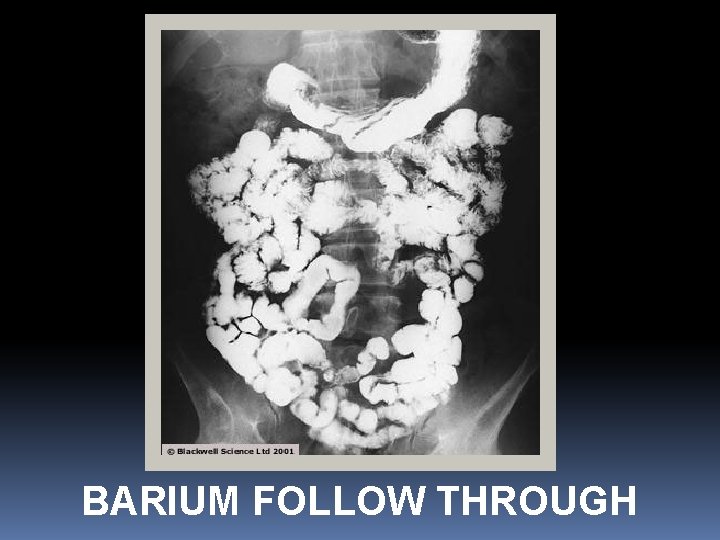

BARIUM FOLLOW THROUGH